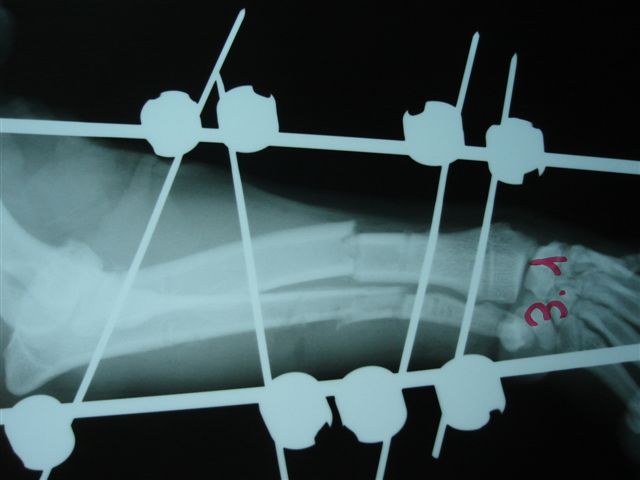

Fijación Externa en IVOT

Fijación Externa

IX CURSO BASICO DE FIJACION EXTERNA.

Casos prácticos alumnos.